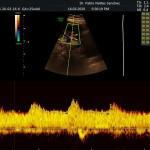

- La vitalidad y el bienestar fetal (Doppler).

- El Doppler de las arterias uterinas maternas y determinación de riesgo para pre eclampsia severa.